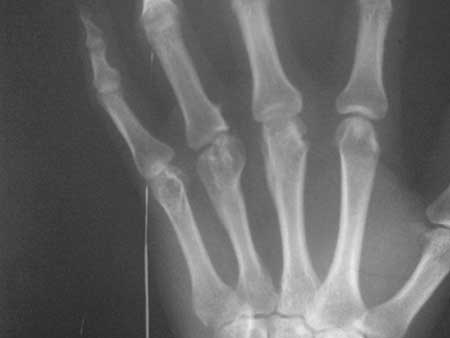

男性患者,31岁,中指和无名指活动障碍,无名指近节指间关节屈曲。

1、三、四掌骨远端陈旧性骨折;2、三、四掌指骨关节创伤性关节炎。